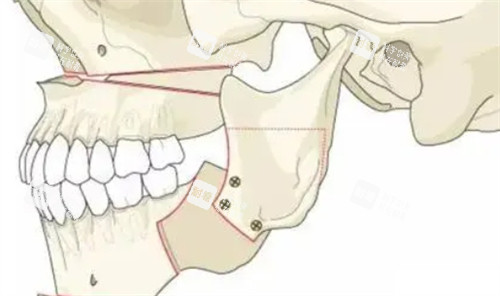

正颌手术则是在正畸治疗进行到一定阶段后进行。外科医生会根据正畸医生提供的牙齿和颌骨的模型、影像学资料等,制定详细的手术方案。手术中,医生会通过正确的操作将颌骨移动到合适的位置,并进行固定。正颌手术能够从根本上解决颌骨发育异常的问题,从而显著改善嘴凸的情况。

传统正颌手术是通过外科手术的方式直接对颌骨进行截断、移动和固定,以达到矫正颌骨畸形的目的。这种手术对于严峻的骨性嘴凸有一定的治疗结果,可以较大程度地改变颌骨的位置和形态。但是,传统正颌手术也有一些不足之处。手术创伤较大,术后修养时间较长,患者需要承受较大的痛苦。而且手术风险相对较高,可能会出现出血、感染、神经损伤等并发症。此外,传统正颌手术在术前规划和手术操作的正确性方面存在一定的局限性,可能无法达到理想的治疗结果。